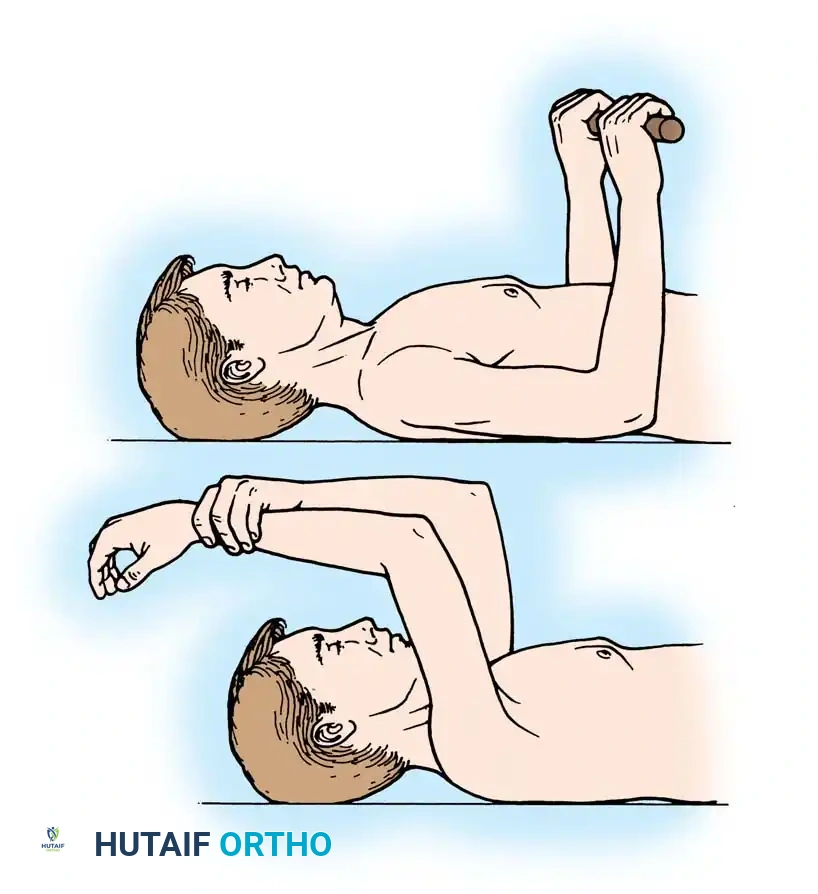

Shoulder Arthroplasty Rehabilitation

- Phase I (0-4 weeks): Sling immobilization. Passive range of motion (PROM) only. Strict avoidance of active internal rotation and passive external rotation beyond 30 degrees to protect the subscapularis repair.

- Phase II (4-8 weeks): Discontinue sling. Begin active-assisted range of motion (AAROM). Initiate isometric deltoid exercises.

- Phase III (8-12 weeks): Progress to active range of motion (AROM) and light resistance training.